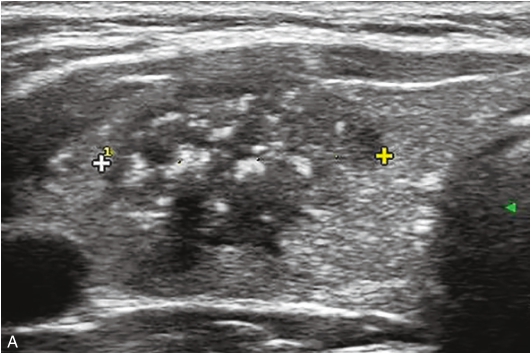

甲状腺左叶上极及下极分别可见一个低回声,大小约为0.8cm×0.9cm×0.6cm,边缘模糊,纵横比>1,内可见多发点状强回声;CDFI示结节内均未见明显血流信号。双侧颈部可见多发肿大淋巴结,其中左侧Ⅲ区可见一个大小为2.2cm×0.8cm、形态规则、淋巴门回声偏心、皮质回声增厚的结节;CDFI示淋巴结内可见丰富血流信号,见图1-9-3。

图1-9-3 甲状腺髓样癌及颈部淋巴结常规超声图像

A.甲状腺左叶上极低回声结节灰阶超声图像;B.CDFI示未见明显血流信号;C.左侧Ⅲ区结节灰阶超声图像;D.CDFI示结节内可见丰富血流信号